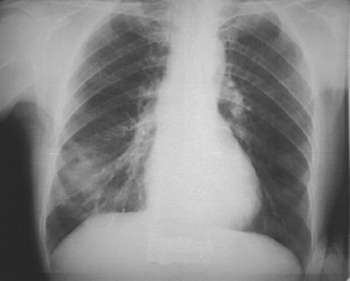

30 жастағы, зиянды әдеті жоқ, науқас дене қызуының 38º-ке дейін көтерілгеніне, қақырық аз бөлінетін жөтелге, жалпы әлсіздікке шағымданды. Ауырғанына 3 күн болған. Тексергенде- рентген суретте төмендегідей өзгеріс бар.Осы науқасты емдеу үшін қандай антибиотикті тағайындаған тиімді?//